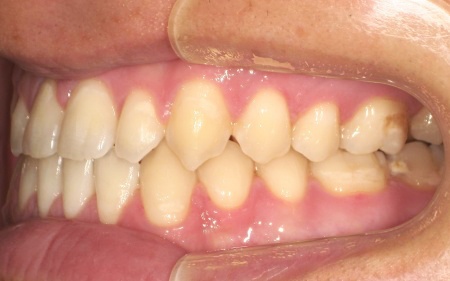

拝見したところ、上下前歯の先端同士が触れ合う「切端咬合(せったんこうごう)」の状態でした。

通常は上前歯が下前歯をわずかに覆うように重なりますが、患者様の場合は上下前歯の先端がほぼ同じ高さで噛み合っているため、受け口のような印象がみられました。

また、上下前歯の接触により下顎を前に出しにくく、後ろへ押し込まれやすい咬み合わせとなっています。

このまま放置すると、前歯の先端が少しずつすり減ったり欠けたりするリスクがあるだけでなく、顎の関節にも負担がかかり、食べ物を噛む機能や発音に影響が出るおそれもあります。